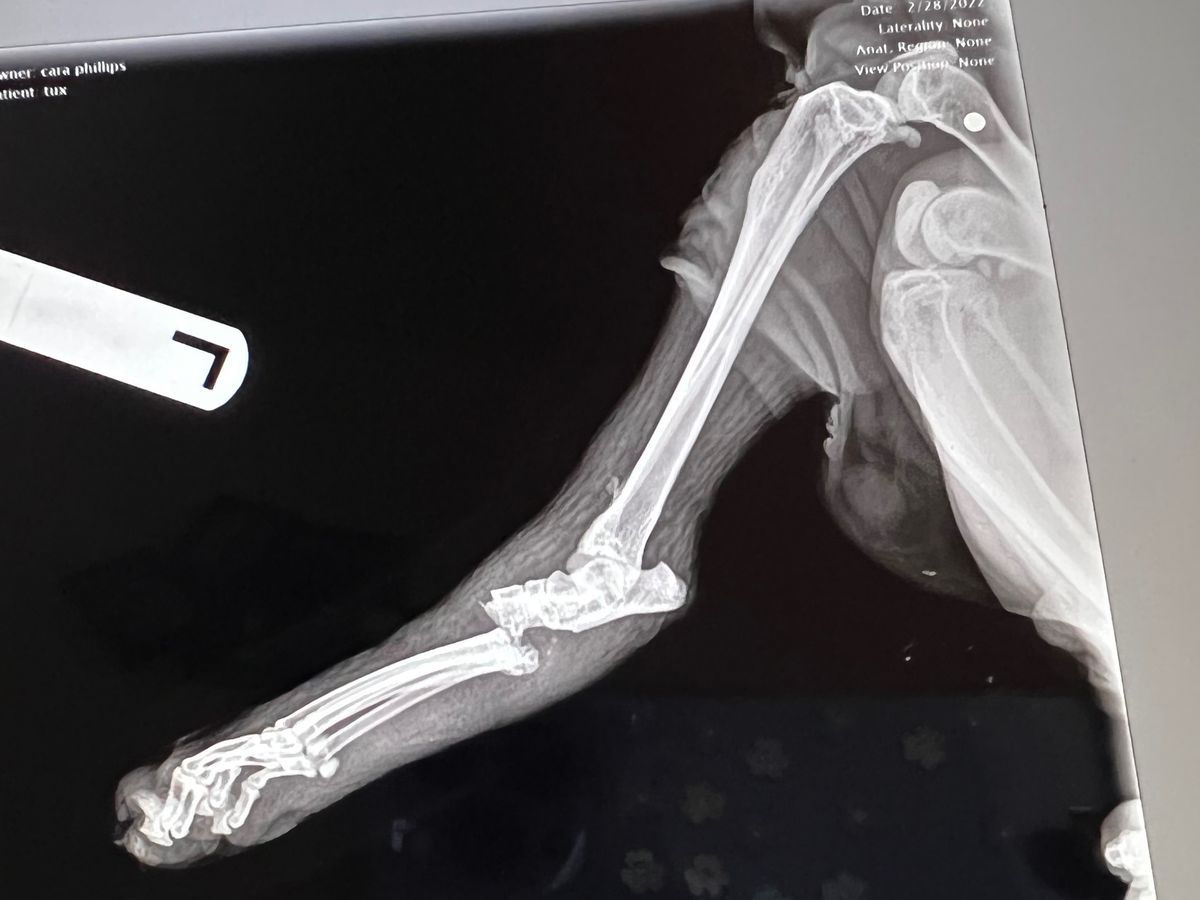

Hello thanks for taking the time to look at my page. My name is Cara and I am trying to save my cat Tux. He needs an urgent and expensive surgery to fix the broken bone, infection in his leg, and remove the BB someone shot into him.

I found him finally and brought him home but he wouldn’t put pressure on his left hind leg and it was swollen twice the size it should be and when he hopped on his 3 good legs his paw would just dangle and swing from side to side.

I took him to the vet ER and then to his vet the next day. None of it has been good news… his infection is really really bad but because it is on the same leg as the one that is broken it can’t be aired out to heal right because it has to be in a splint for the broken bone.

On top of all off this we found out that someone SHOT him with a BB gun! The BB is still stuck inside him and you can see it in the x-Ray.